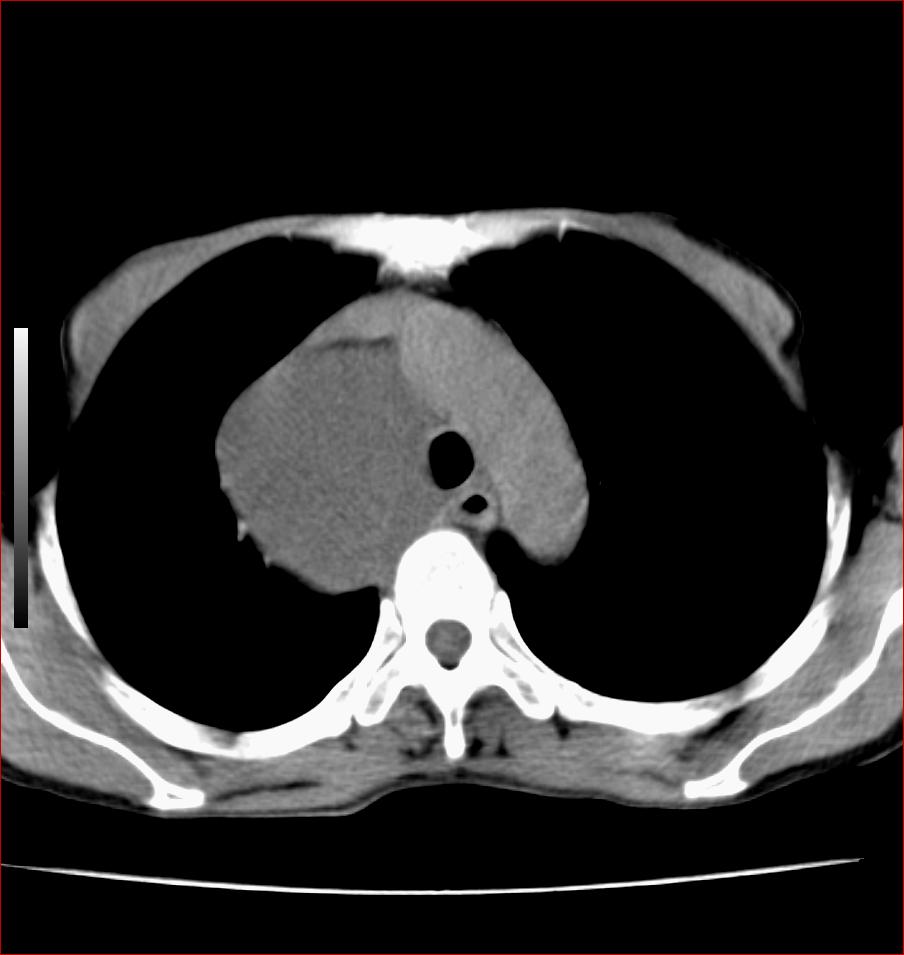

标题: CT17110:F56Y,纵隔囊肿;胸腺?淋巴?请各位老师看看 [打印本页]

标题: CT17110:F56Y,纵隔囊肿;胸腺?淋巴?请各位老师看看

女性患者 56 咽痛伴声嘶10+天入院。

纵隔囊肿,气管来源可能性大

病变紧贴气管右壁,两者相互压迫,考虑支气管囊肿!

见相互挤压征,考虑气管囊肿,建议ct增强扫描

纵隔前肠性囊性,支气管囊肿可能性大